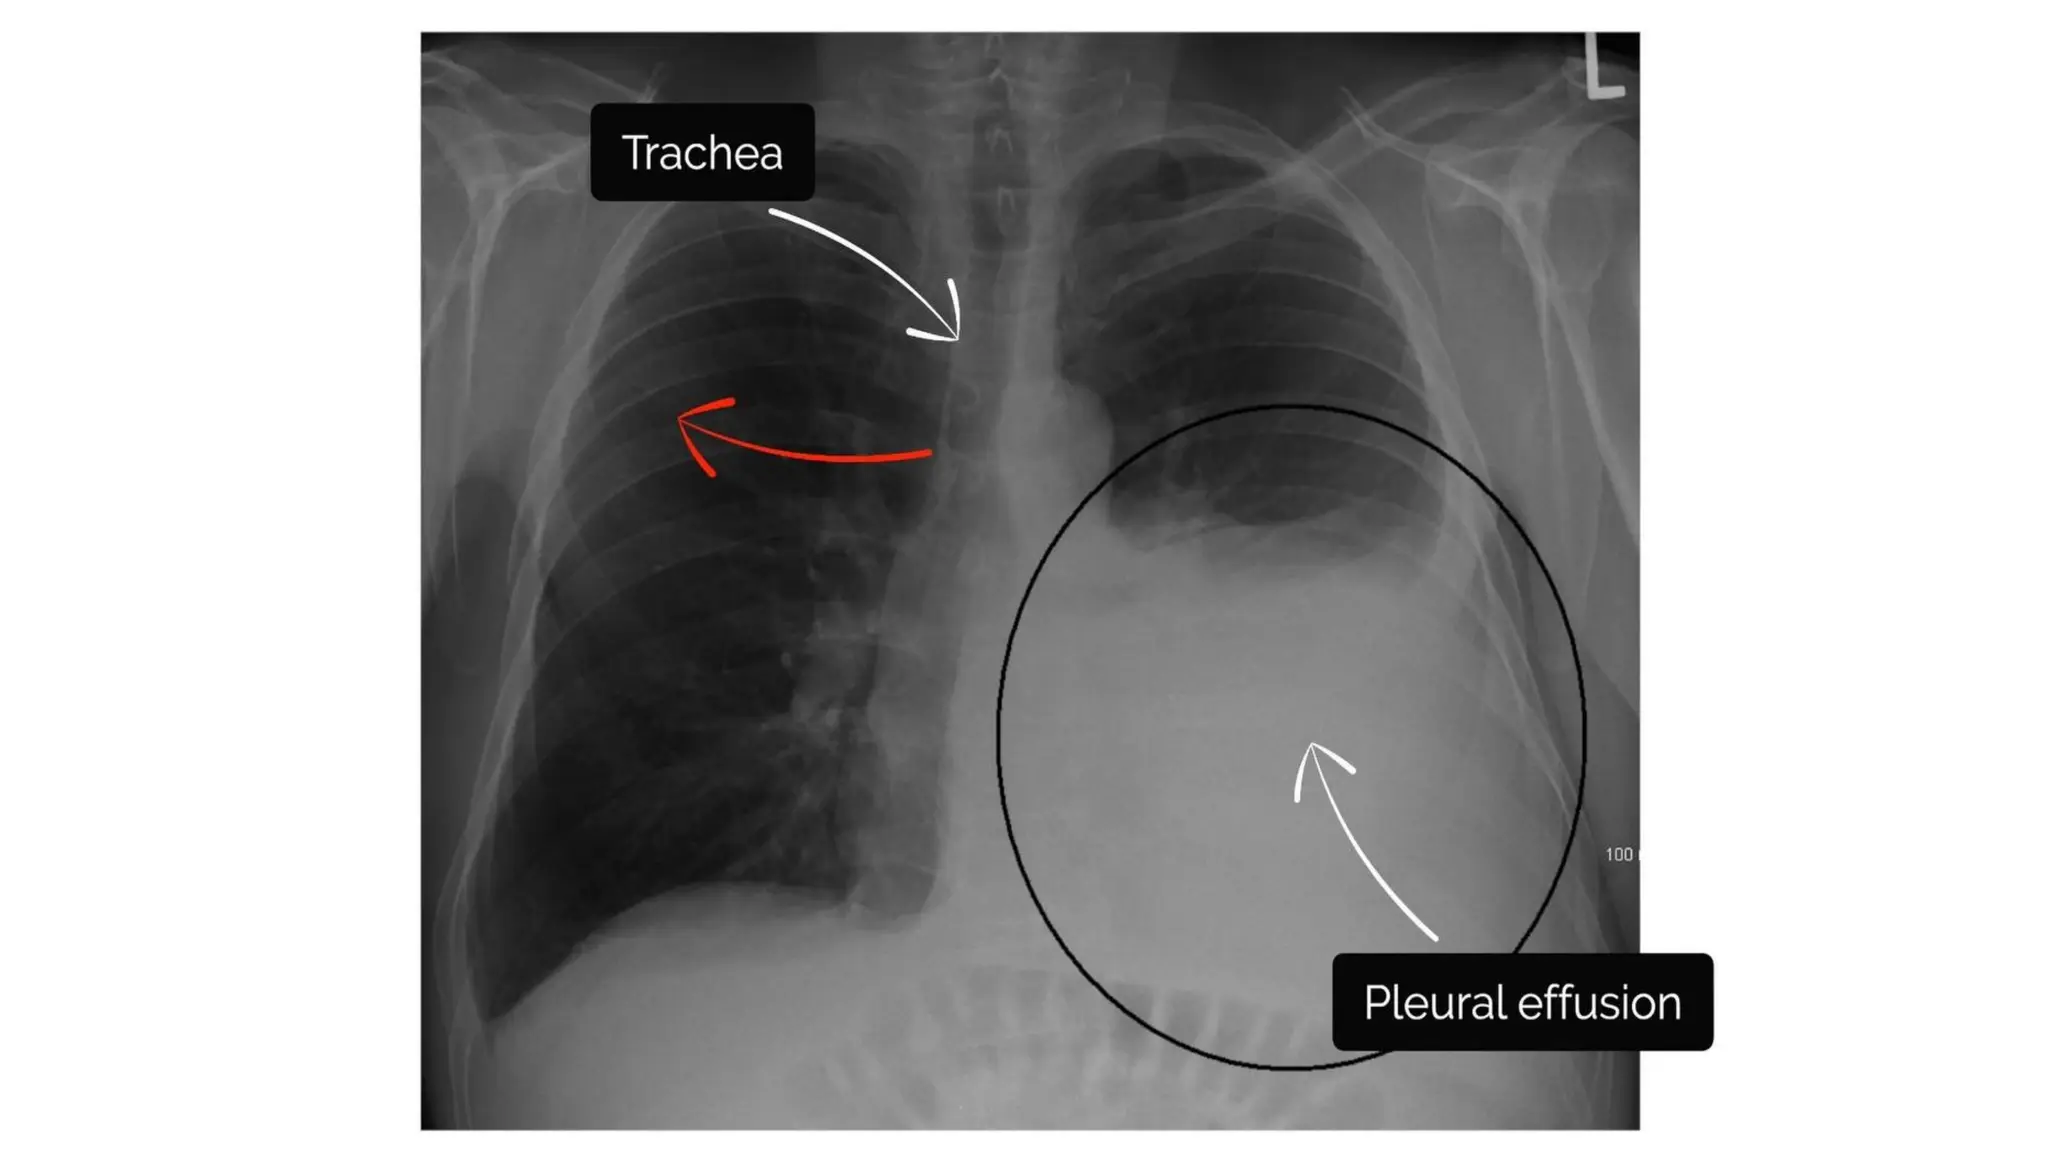

Trachea

Inspect the trachea for signs of deviation

True deviation Apparent deviation

Large pleural effusion

Tension pneumothorax

Lobar collapse

Rotation of the patient

Costophrenic angles

• The costophrenic angles reflect the dome

shape of hemidiaphragm as it meets the

lateral chest wall.

• The loss of this angle is termed as

costophrenic blunting & causes

includes:

Pleural effusion

Consolidation

Hyperinflation (e.g. asthma copd)